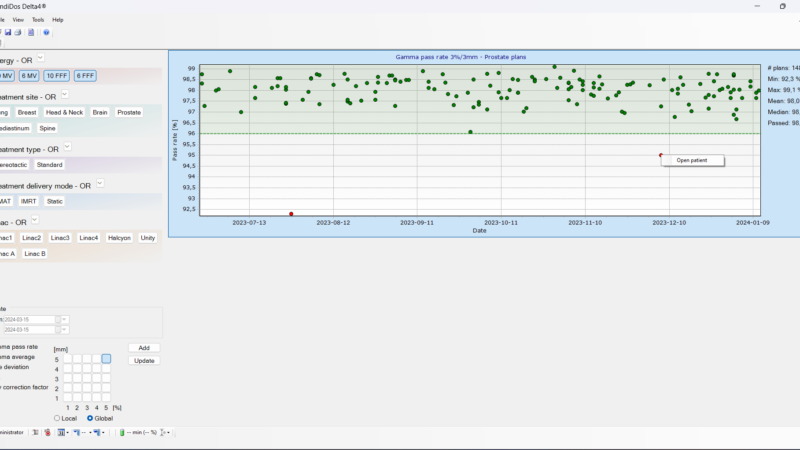

Delta4 software

Streamline your workflow

Delta4 software

Instant and accurate analysis

Delta4 Software

Instant Results